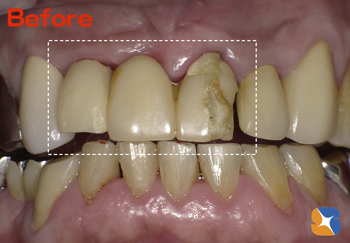

他院より70代の男性。主訴は「前歯のブリッジが割れて、唇に引っ掛って痛い。もう修理はやめて、一からやり換えて欲しい。頼みます」でした。

Dr「分かりました。古いブリッジを外し、土台となる歯をきっちり手直し(補強)してから仕上げていきます。多少期間がかかりますが、御了承ください」 続きを読む